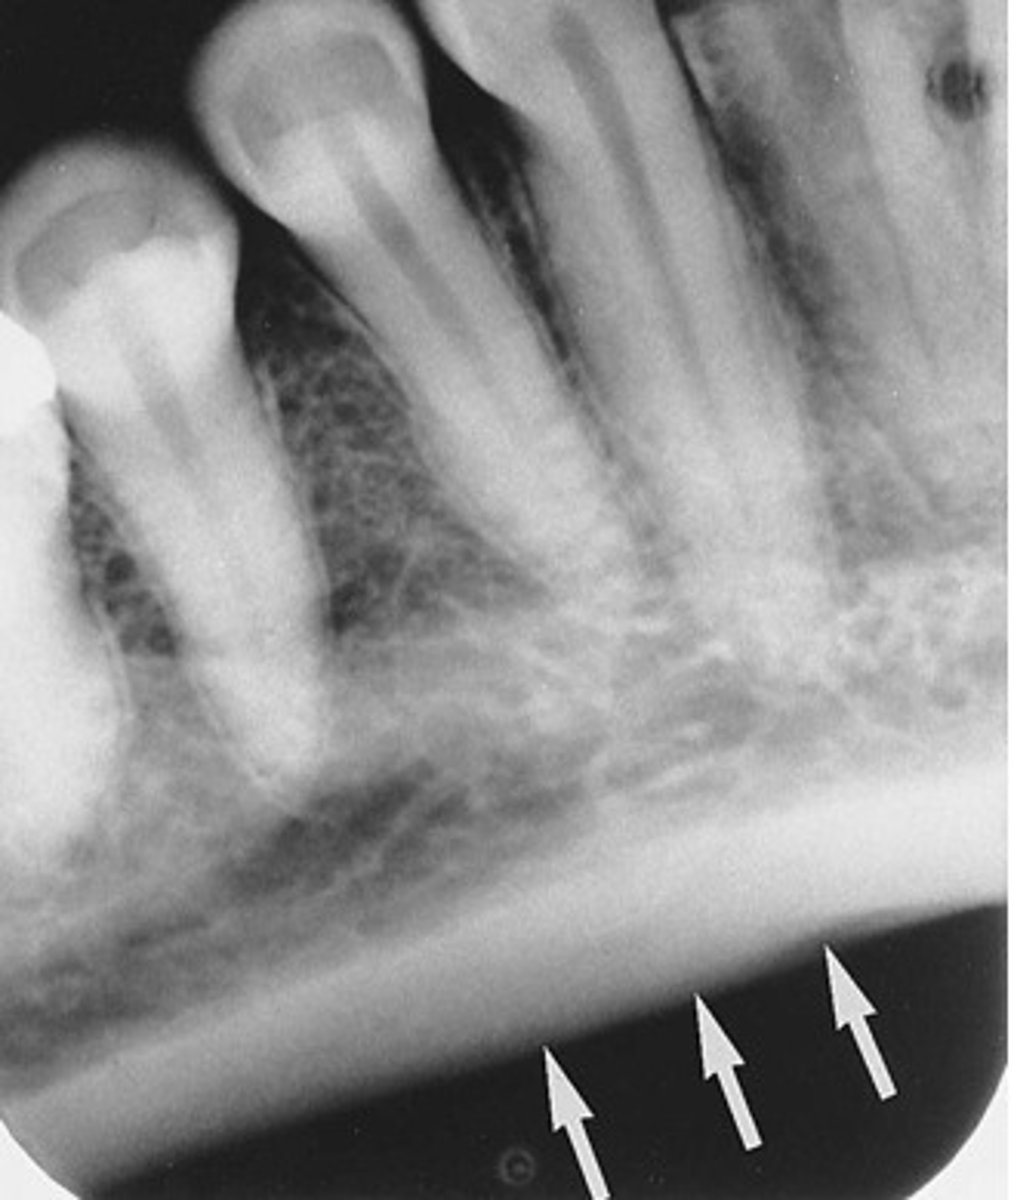

external oblique ridge

dense white line distal to the last molar and moving across root of molars

internal oblique ridge

located below the external oblique ridge

less dense

ridge of bone that extends across roots

mandibular canal

border on top and bottom by a white line

passageway for nerves and blood vessels